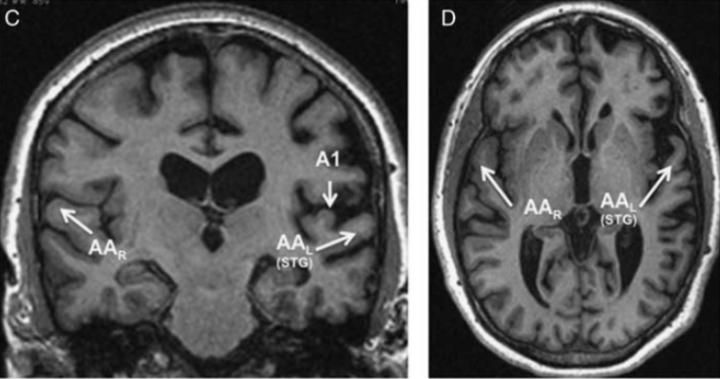

image: This is an MRI brain scan from a patient in the study.

The study, published March 21 in the journal Cognitive and Behavioral Neurology, allowed the scientists to identify a previously little-studied area in the left brain that seems specialized to process auditory words.

"It doesn't happen that often that you just get an impairment in one area," Weintraub said, explaining that the brain is compartmentalized so that different networks share the job of seemingly easy tasks, such as reading a word and being able to say it aloud. "The fact that only the auditory words were impaired in these patients and their visual words were untouched leads us to believe we've identified a new area of the brain where raw sound information is transformed into auditory word images."